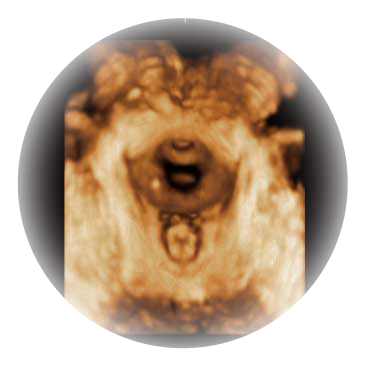

• S-Live Silhouette光影成像

可同时显示组织结构表面和内部的轮廓信息,达到透视效果,为临床提供更丰富的诊断信息。